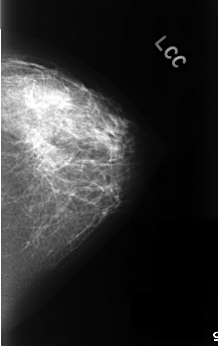

C_0330_1.LEFT_MLO

C_0330_1.LEFT_CC

LEFT_MLO LINES 4568 PIXELS_PER_LINE 2784 BITS_PER_PIXEL 12 RESOLUTION 50 NON_OVERLAY

LEFT_CC LINES 4496 PIXELS_PER_LINE 2824 BITS_PER_PIXEL 12 RESOLUTION 50 NON_OVERLAY